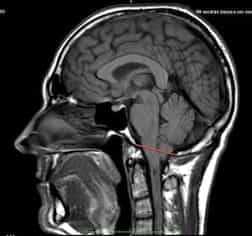

Рисунок 2.- МРТ пациента в 8 и 20 месяцев, на втором снимке можно наблюдать опущение миндалин мозжечка, которое появилось уже после первого МРТ. Huang P. “Adquired” Chiari I malformation. J. Neurosurg 1994. Это указывает на то, что, помимо наследственного и генетического фактора, существует фактор приобретенного заболевания.